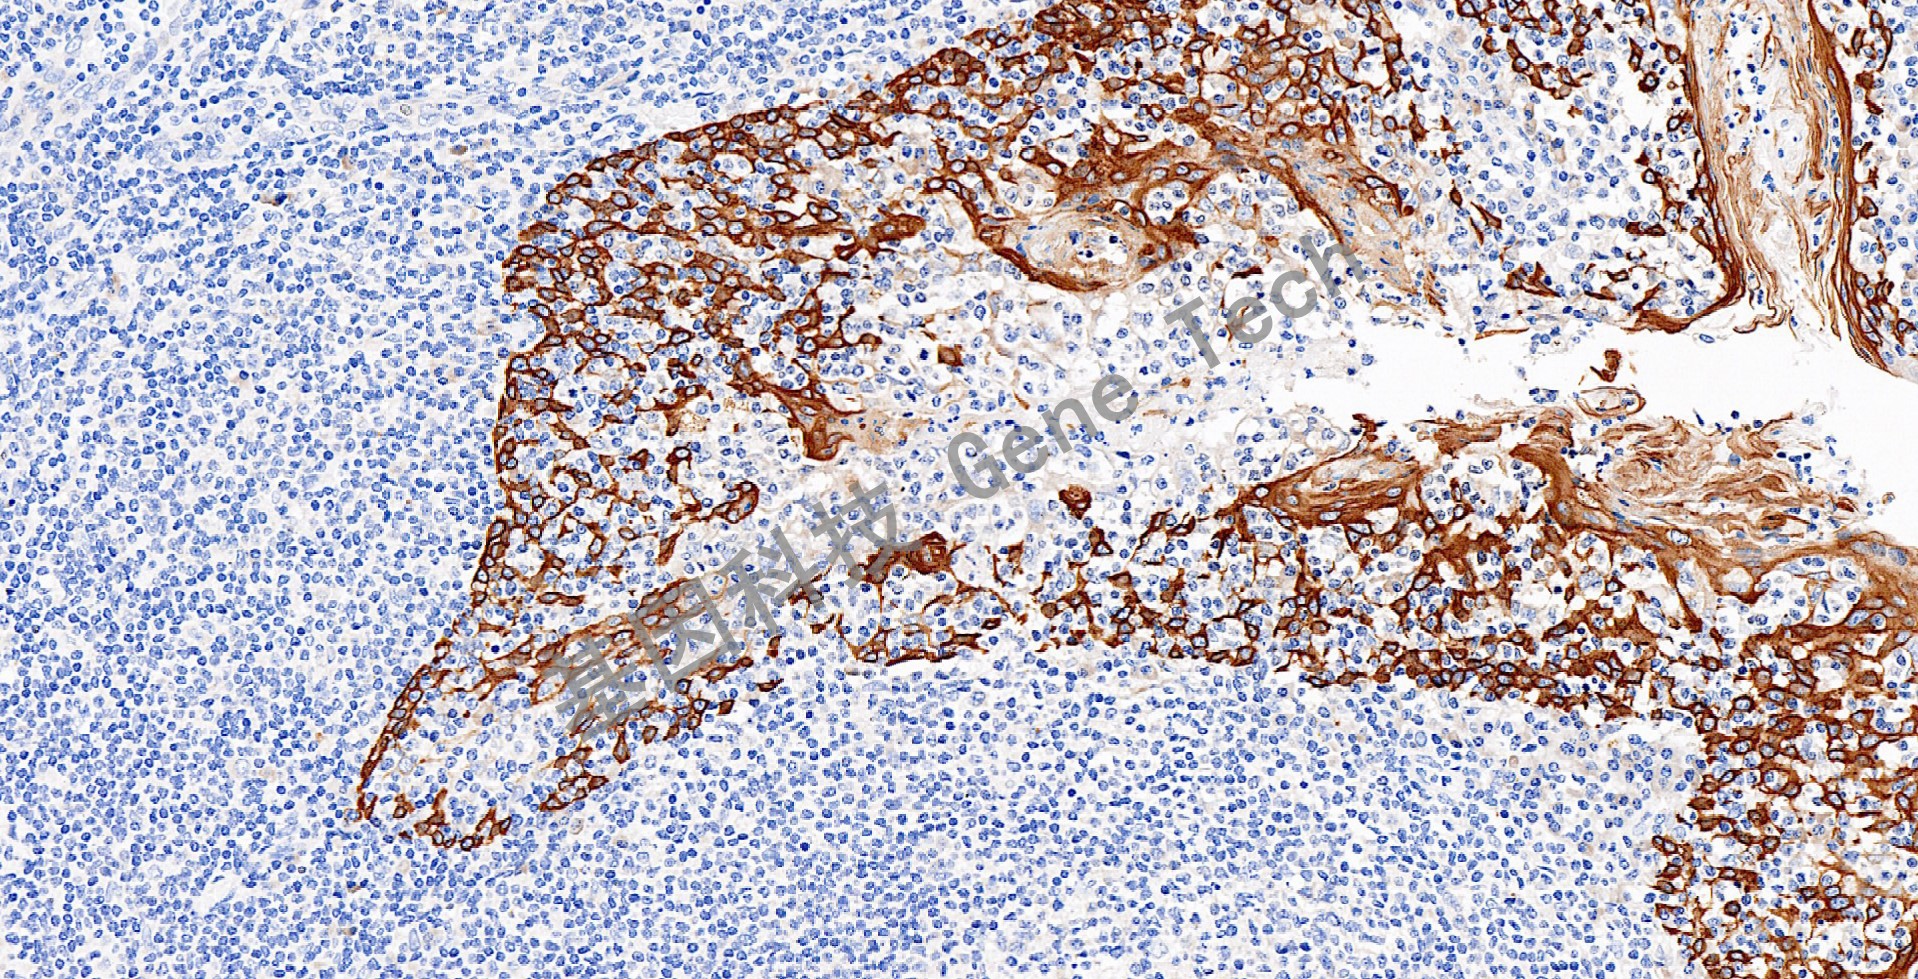

扁桃体石蜡切片,用 CK16(GT2228)染色,细胞浆阳性,DAB 显色。